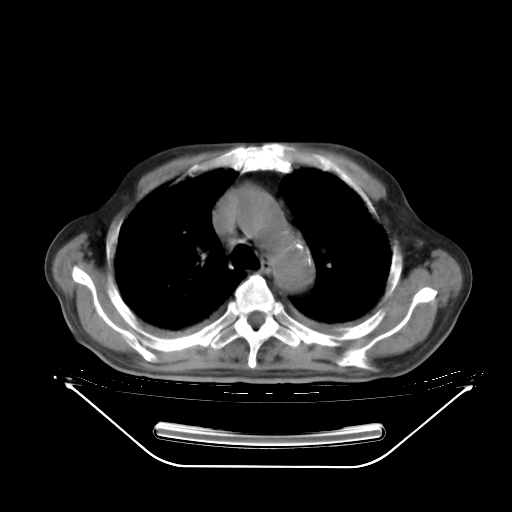

今天复查肺部CT,发现双肺广泛磨玻璃样改变。所以我把3月19日和5月9日相隔50天的肺部CT上传。请大家会诊。

5月9日肺部CT(在4月27日齐鲁医院肺部CT描述部分肺组织磨玻璃样改变,12天后肺组织广泛磨玻璃样改变)

2009年5月9日肺部CT

大致读了系列胸部CT:纵隔窗无明显异常,肺窗:从4、27至今:主要是双肺中下野外带可见毛玻璃样改变,目前处于急性肺泡炎阶段,至于原因考虑1、结替组织或胶原血管性疾病所致?2、恶性疾病如恶组在肺部所致的表现或细支气管肺泡癌?3、药物或其它原因如肺蛋白沉着症所致肺泡炎目前不太可能?总之,明天就去请我院的呼吸科、感染科、血液科和临免专家会诊哈。